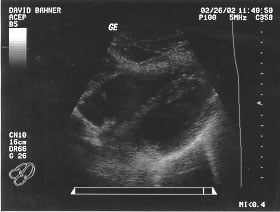

Cardiac - Subxiphoid view (unlabeled)

Cardiac - Subxiphoid view (labeled)